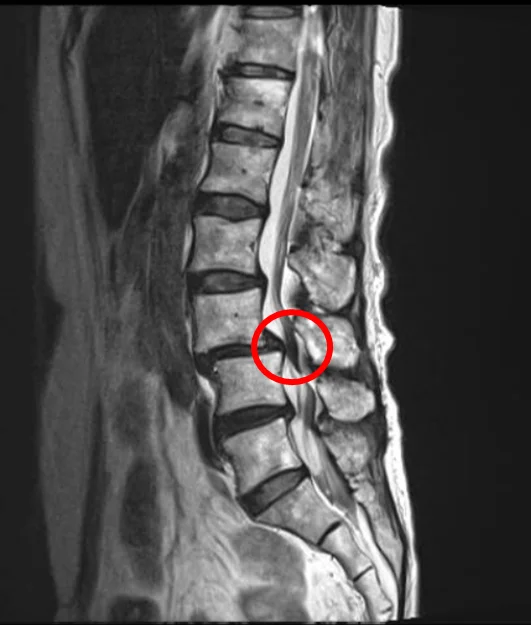

При стенозе позвоночного канала вследствие деформации позвонков и связок позвоночный канал сужается. В результате возникают боли и онемение в пояснице и ногах. Типичный симптом стеноза поясничного отдела позвоночника – перемежающаяся хромота, периодическое возникновение при ходьбе болей и онемения в ногах, вынуждающих остановиться.

Стеноз позвоночного канала